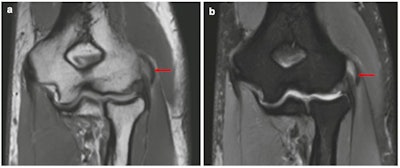

Coronal proton density (A) and proton density fat-suppressed (B) show edema and thickening of common extensor origin in keeping with lateral epicondylitis (arrow).